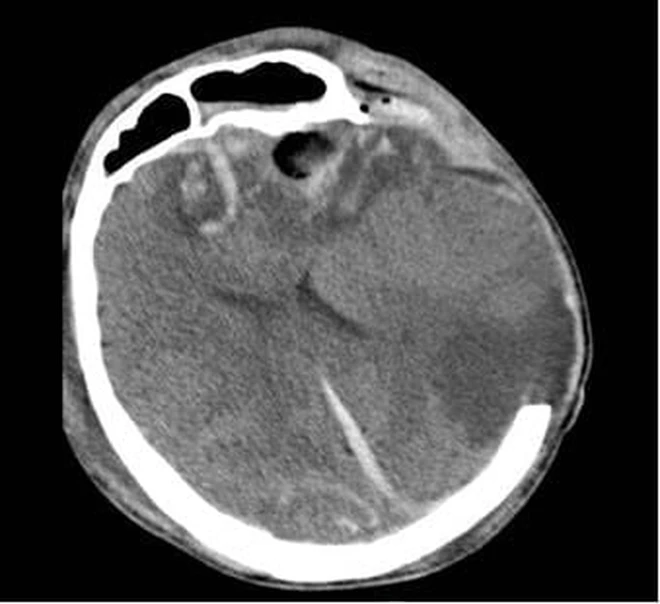

Phim CT não của 2 bệnh nhân

Tại Bệnh viện Nhân dân 115, bệnh nhân G.A nhập viện trong tình trạng hôn mê sâu, phải thở máy nội khí quản. Kết quả chụp CT sọ não cho thấy dập não xuất huyết rải rác nhiều vị trí, phù não lan tỏa nặng, tiên lượng rất dè dặt, nguy cơ tử vong cao. Bệnh nhân được điều trị tích cực tại Đơn vị Hồi sức ngoại khoa, Khoa Gây mê Hồi sức với sự theo dõi sát sao của ê-kíp chuyên môn.

Người mẹ, bà G.N. cũng trong tình trạng rối loạn tri giác, dập não thái dương lượng lớn. Sau hội chẩn kỹ lưỡng, các bác sĩ quyết định lựa chọn phương pháp điều trị bảo tồn nhằm hạn chế tối đa tổn thương thứ phát. Hướng điều trị này cho thấy hiệu quả rõ rệt khi người bệnh dần tỉnh táo, cải thiện khả năng giao tiếp và chức năng ngôn ngữ. Sau 10 ngày điều trị tại Khoa Ngoại thần kinh, bà G.N. hồi phục tốt và được xuất viện.